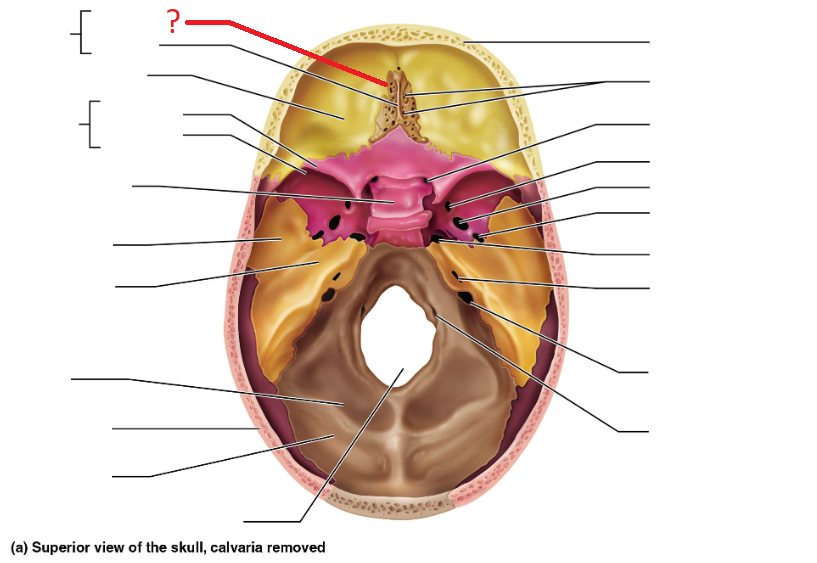

Ethmoid bone

Crista galli

Cribriform plate

Greater sphenoid wing

Lesser sphenoid wing

Sella turcica, protects pituitary gland

Foramen magnum (superior interior view)